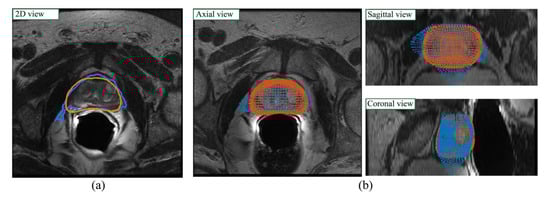

2.4.2. ASM Model Application on Network Output

2.4.3. Post-Processing

- Triangulation: the Alpha Shape Triangulation method is employed to divide the 3D surface into a variable number of triangles, with α = 30.

- 2D slices definition: to obtain the final 2D slices of the segmentation, the volume is divided into a number of planes whose z-coordinate corresponds to the number of slices. Then, similarly as to what was described previously, new vertices of the segmentation are found by computing the intersection between each ray and each triangle and taking the furthest point from the center, which is a first approximation of the points on the outermost surface.

- Final 3D volume reconstruction: the final 3D volume is obtained by stacking the 2D slices together, employing a hole-filling operation, and then a 3D morphological closing (spherical structural element, radius = 4). The post-processed binary volume is finally downsampled to the original resolution.